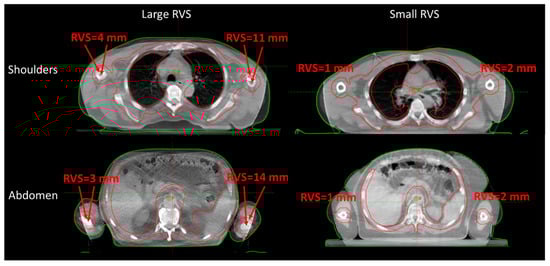

| Shoulders | 2.8 (1.6, 4.2) | 2.9 (0, 6.2) | 5.1 (0, 8.0) |

| Abdomen/Arms | 4.7 (3.0, 6.4) | 7.0 (4.5, 10.0) | 7.3 (3.3, 9.8) |